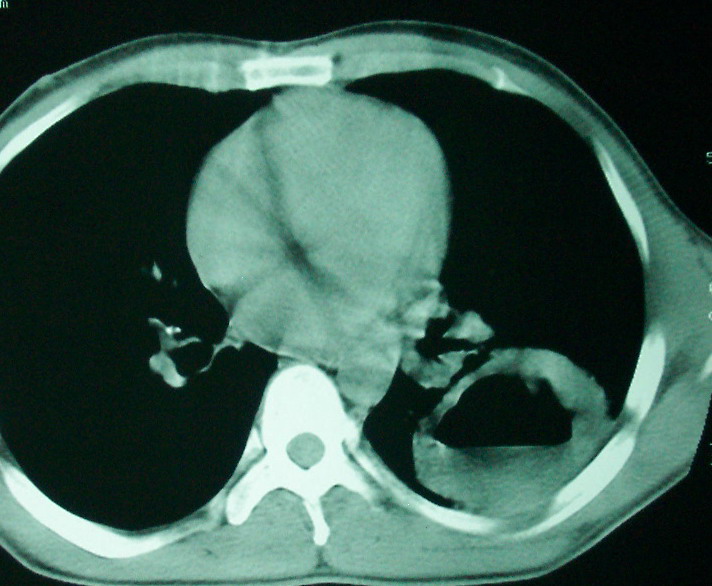

m      37y      发热   咳脓痰月余      ct肺脓肿但住院抗炎治疗后双肺内结节不知该如何解释

治疗后见左肺下野病灶较前缩小但双肺内结节影似无变化请较各位老师该如何下结论    治疗前wbc14.5 治疗后wbc 11.0

如果你仔细的同层面对比,你会发现所有的病灶均有比较明显的吸收、缩小。病变的形态,特别是脓肿的形态、壁的厚薄、内壁均有很大的变化,均在往好的方面发展。与临床症状、血像均符合,治疗效果比较显著,就是肺脓肿并双肺的化脓性炎症灶。

实在不放心,可以短期内再复查,应该变化更明显。